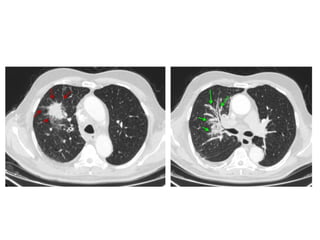

Distribution of UIP, the distribution is subpleural with an apicobasal

gradient (red area in a), CT shows honeycombing (green areas

in c), reticular opacities (blue areas in c), traction bronchiectasis

(red area in c), and focal ground-glass opacity (gray area in c)

Honeycombing & traction bronchiectasis in UIP

Honeycombing comprises reticular densities caused by the thick walls of the cysts.

Whenever you see a chest film with long standing reticulation with a lower lobe and

peripheral preference

A, Unenhanced axial high-resolution CT through left mid (A) and lower (B) lung

show peripheral honeycombing, which is greatest in lower lobe,

accompanied by traction bronchiectasis and scattered peripheral reticular

opacities. Honeycombing is most prominent feature in this patient, typical for

idiopathic pulmonary fibrosis